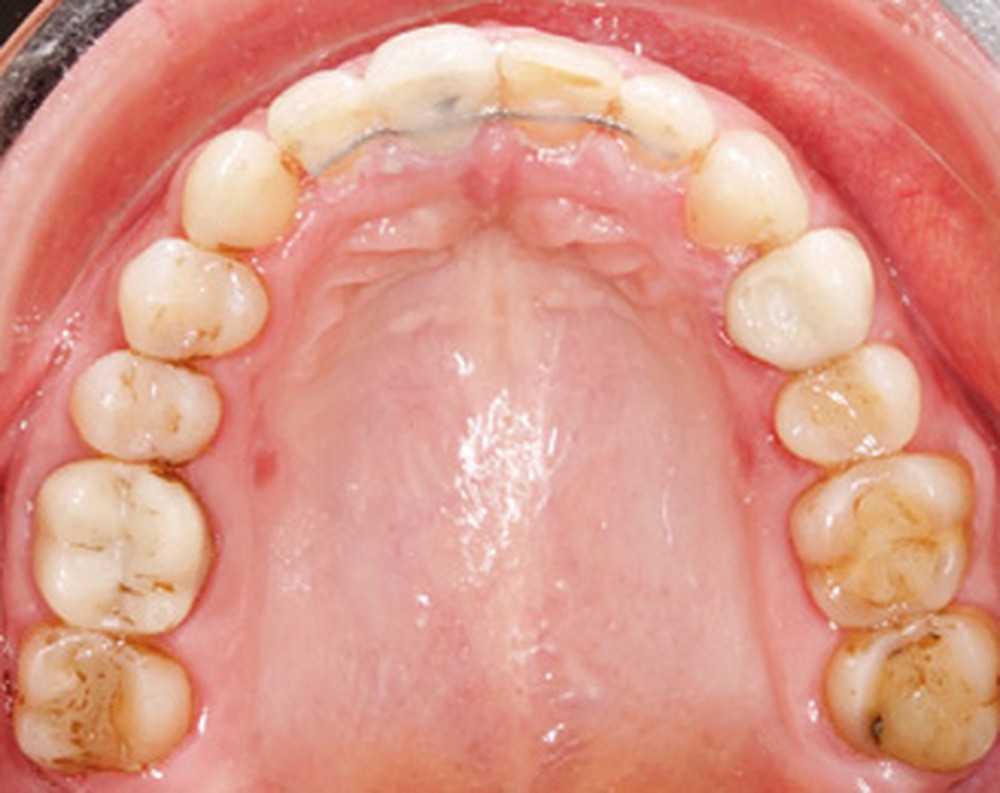

Examen endobuccal (fig. 2a-e)

L’arcade maxillaire est asymétrique et parabolique. Elle présente une mésio-position du secteur 1. On note des rotations mésio-vestibulaire de 13 et disto-vestibulaire de 23 et une palato-version incisive. Les restaurations prothétiques sur 11, 16 et 24 semblent à refaire. L’arcade mandibulaire est asymétrique et parabolique avec une couronne sur implant en 36.

Dans la dimension transversale, on constate une endoalvéolie maxillaire. Dans la dimension sagittale, on observe une classe II plus importante à droite où elle est complète de 5 mm. Le surplomb est absent et la supraclusion totale (6 mm) par supra-alvéolie mandibulaire.